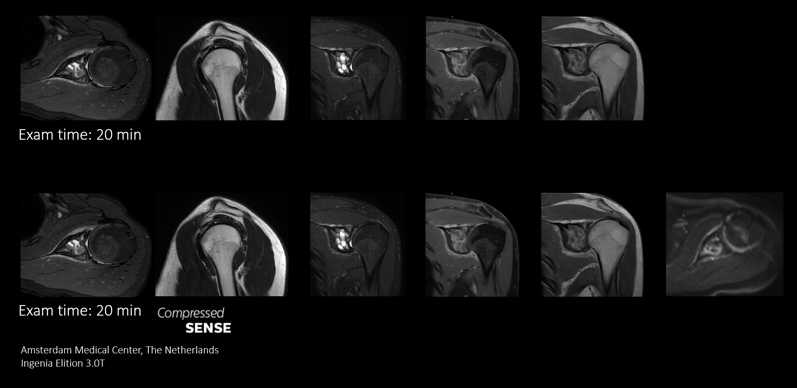

Compressed SENSEを使用することにより、同じMR検査枠でより多くの情報を取得できる高い柔軟性が得られます。また、高速化によって、機能的シーケンスなど特殊なシーケンスをさらに追加してより有用な診断情報を取得することができます。

このケースでは、同じ検査枠内にシーケンスを追加して、診断能を向上させています。ここでは、従来のTSEシーケンスに加えて、診断に役立つ追加の情報が含まれたDWIシーケンスを同じ検査枠内に追加しています。

Compressed SENSEを使用した高速化スキャンによって時間を節約できるので、高画質の画像を取得して診断能を高めるためのシーケンスを追加できます。